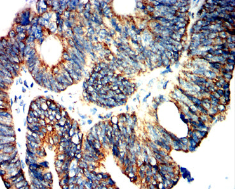

CD319 Mouse Monoclonal antibody[7A8D5]

IHC    1/100 - 1/500